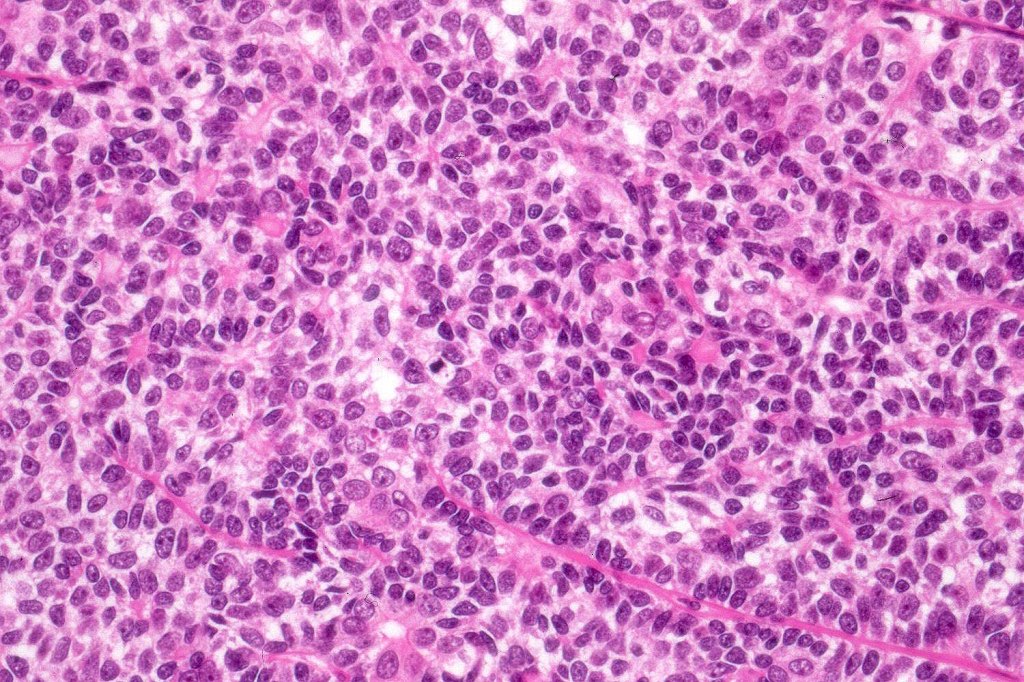

Histological features

•Pre-existent spiradenoma

•Malignant component shows loss of dual cell population, increased mitotic activity, atypical mitoses & necrosis

•Perineural infiltration & LVI may be present